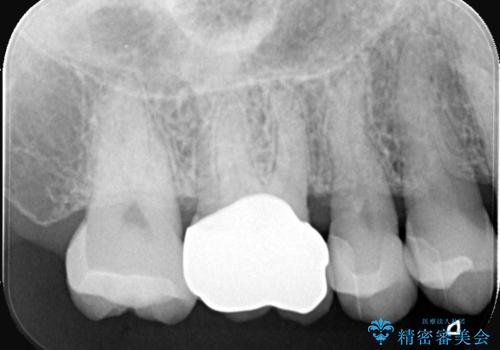

- 左上奥歯に入っている金属の詰め物(メタルインレー)の見た目を改善したいという主訴でご来院されました。お口の中の金属をなくしたいという患者様のご希望を踏まえ、天然歯に近い色と質感を持つセラミックインレーに交換する治療計画を立案。これにより、見た目の改善だけでなく、金属アレルギーのリスクを排除したメタルフリーの環境を実現することを目指しました。

治療では、まず古い金属のインレーを慎重に取り外しました。金属の下に隠れていた虫歯の再発がないかを確認し、歯を丁寧に形成。その後、精密な型取りから患者様の歯の色に合わせたオーダーメイドのセラミックインレーを作製しました。セラミックは、自然な光の透過性を持つため、周囲の歯と区別がつかないほどの美しい仕上がりとなります。適合性の高いセラミックインレーを装着することで、再発のリスクを抑えつつ、長年のコンプレックスだった銀歯がなくなり、笑顔でも気にならない自然な奥歯を取り戻していただけました。